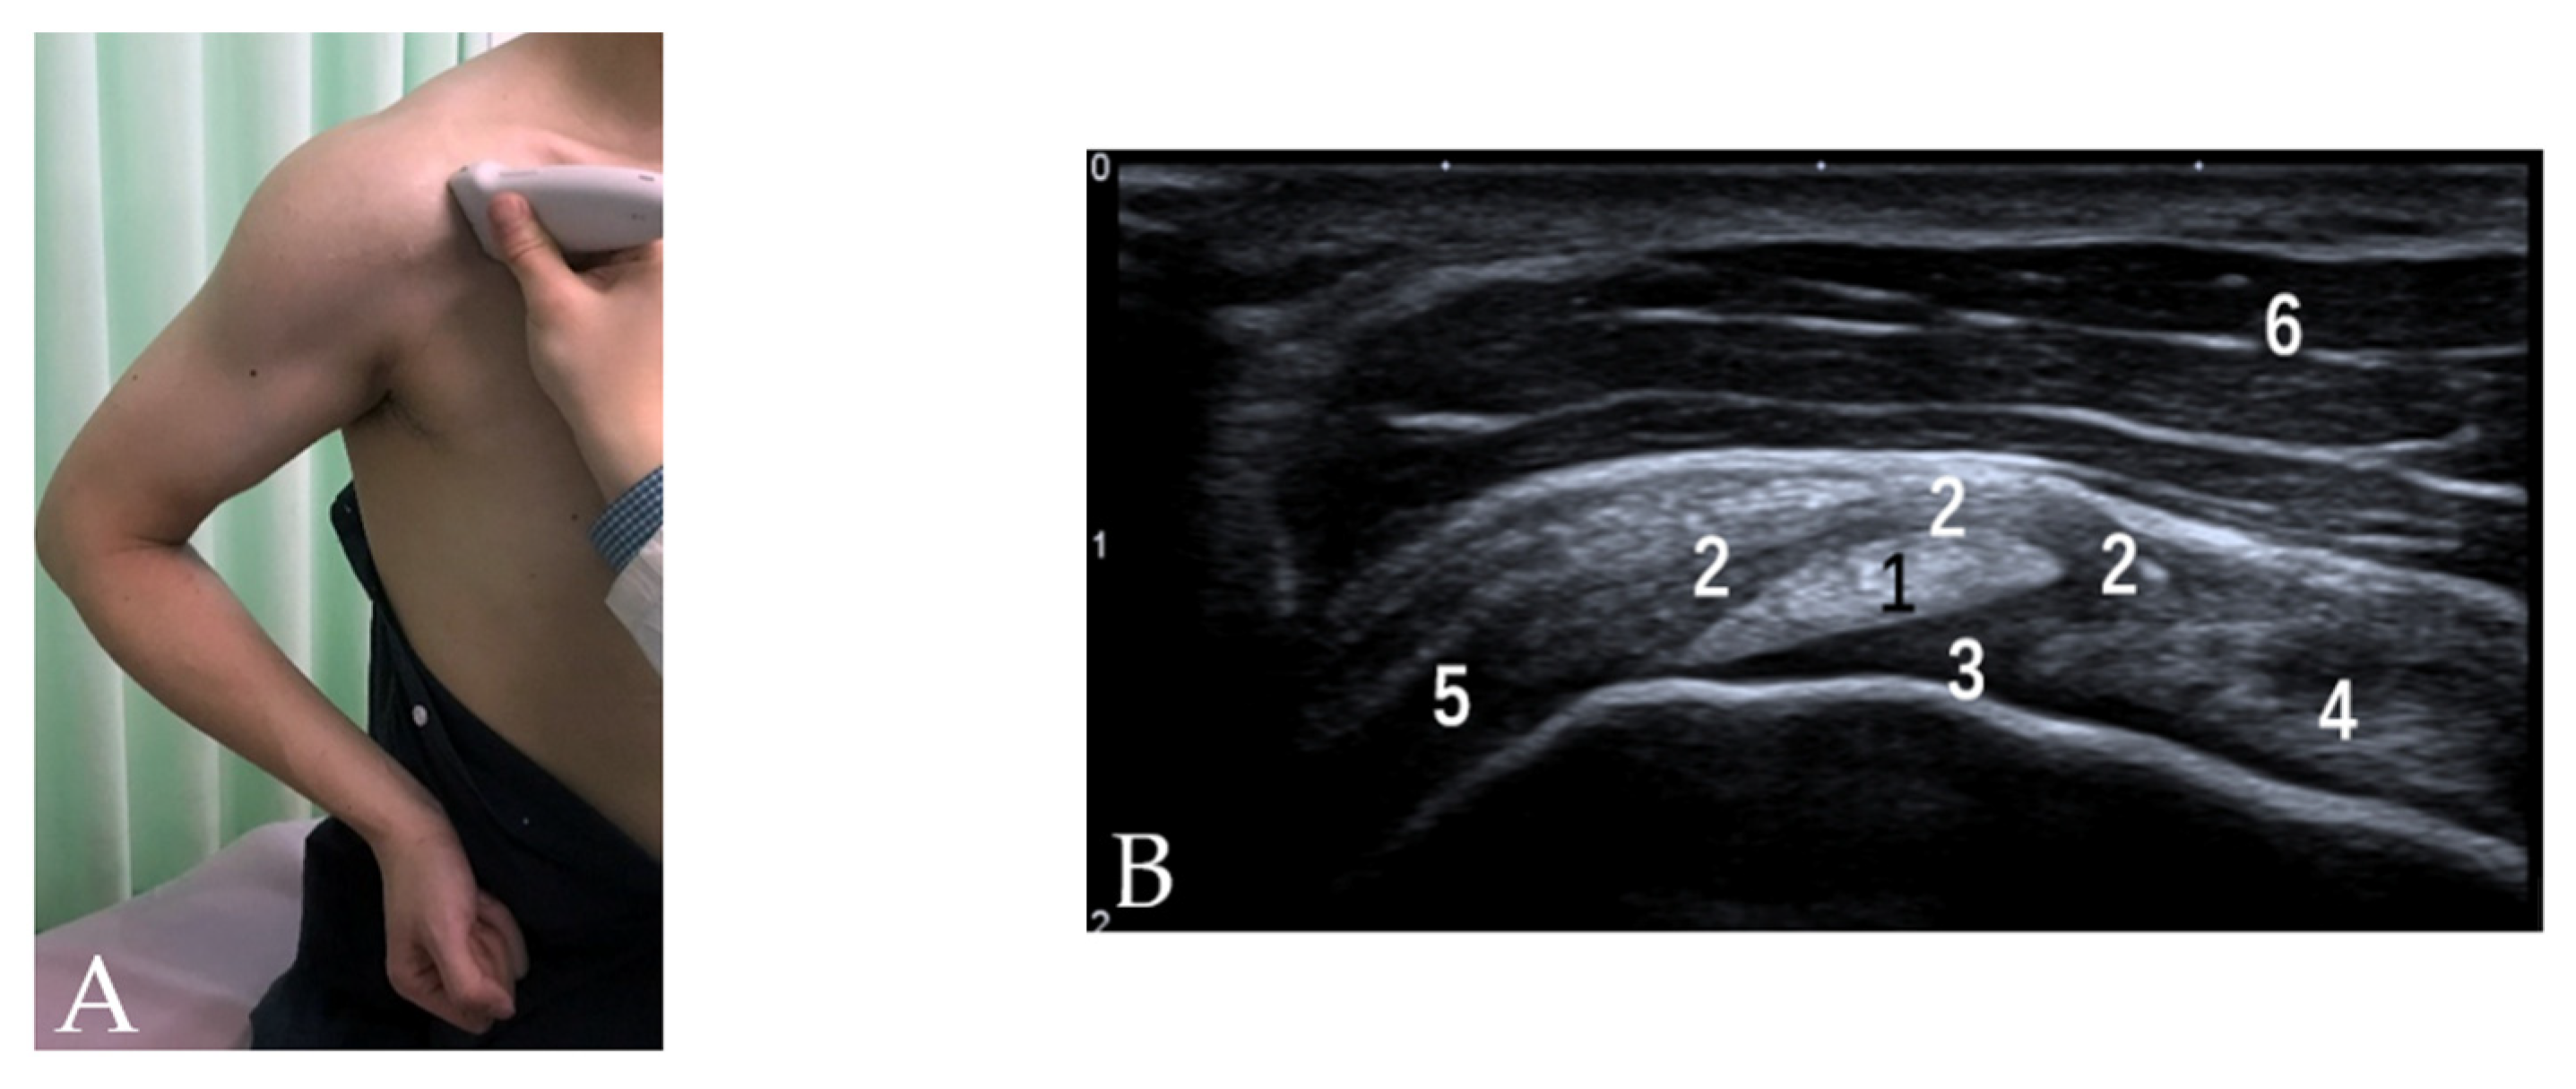

3.1. Rotator Interval, CHL and SGHL

3.2. Bicipital Groove Morphology and Cross-Sectional Area

3.3. SSC and SSP Tendons

3.4. Tendon of PM

3.5. Tendons of LD and TM